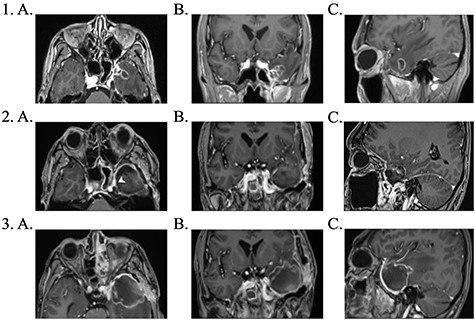

Brain magnetic resonance imaging (MRI) study with contrast revealed an irregular enhancing mass within the left temporal lobe measuring 3 × 2.6 × 2cm with significant surrounding parenchymal oedema (Fig. 1). In addition, enhancement of the adjacent dura extending to the left temporal fossa, pterygoid muscle and left sphenoid sinus was observed.

1. Pre-operative contrast enhanced brain MRI: (a) T1 axial view with enhancing lesion; (b) T1 coronal and (c) T1 sagittal. 2. First post-operative contrast enhanced brain MRI showing resection of lesion: (a) T1 axial. Arrow: dural enhancement of sphenoid sinus; (b) T1 coronal and (c) T1 sagittal. 3. Second post-operative contrast enhanced brain MRI following endoscopic re-resection: (a) T1 axial; (b) T1 coronal and (c) T1 sagittal.

Due to liver function derangement from voriconazole, the antifungal agent was changed to posaconazole. The patient completed a total of 12 months antifungal therapy. Subsequent serial MRI imaging showed good response to therapy with no further recurrence.